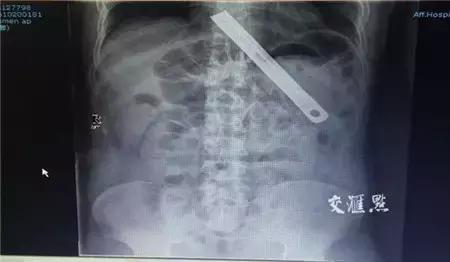

最近有一条新闻,镇江一男子因情绪失控生吞18公分刀片,后被送至江苏大学附属医院,经过医院多科医生通力合作,在胃镜下将这根长约18公分的刀片完整取出。神奇的是,除了食管局部有些出血外,患者竟安然无恙。

▲X光片中,胃里的刀片清晰可见

为了确保安全,医院集中消化内科、普外科、麻醉科多名专家现场分析并梳理可能的出现的问题。经过分析,刀片太长,而且锋利程度未知,在取出过程中,遇到食管与喉管相接处这样的“弯道”时,就十分困难。并且,因为刀片没有弹性,强行“拐弯”只会造成食管的划伤,严重的话会造成消化道大出血。经过商讨,院方决定在拐弯处将患者下颌处往上抬,把弯道拉直,便于取物。医生还找来了耳鼻喉科专用的大异物钳。麻醉后,刀片在胃镜下被缓缓取出,最终一次成功。经过测量,此刀片达18厘米!